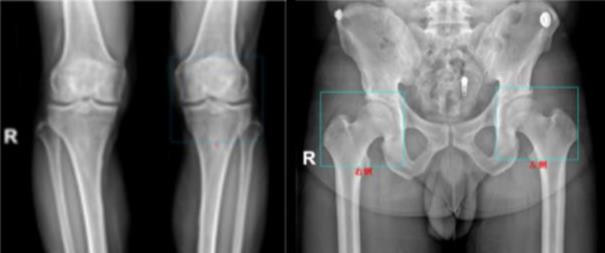

面对市场上多样的筛查技术,如何选择适合自身的体检方案呢?据悉,在骨密度检测领域,爱康集团提供的QCT骨密度人工智能检测,因其可在胸部CT扫描时同步完成骨密度测量,便捷高效且精准度更高,正成为越来越多人的新选择。同时,爱康联合合作伙伴推出的“骨力宝”人工智能膝关节、髋关节健康评估,借助人工智能与大数据分析,能够更早地揭示骨关节退行性变化的趋势,为公众提供了一体化的骨健康管理解决方案。

爱康骨力宝人工智能膝关节、髋关节健康评估